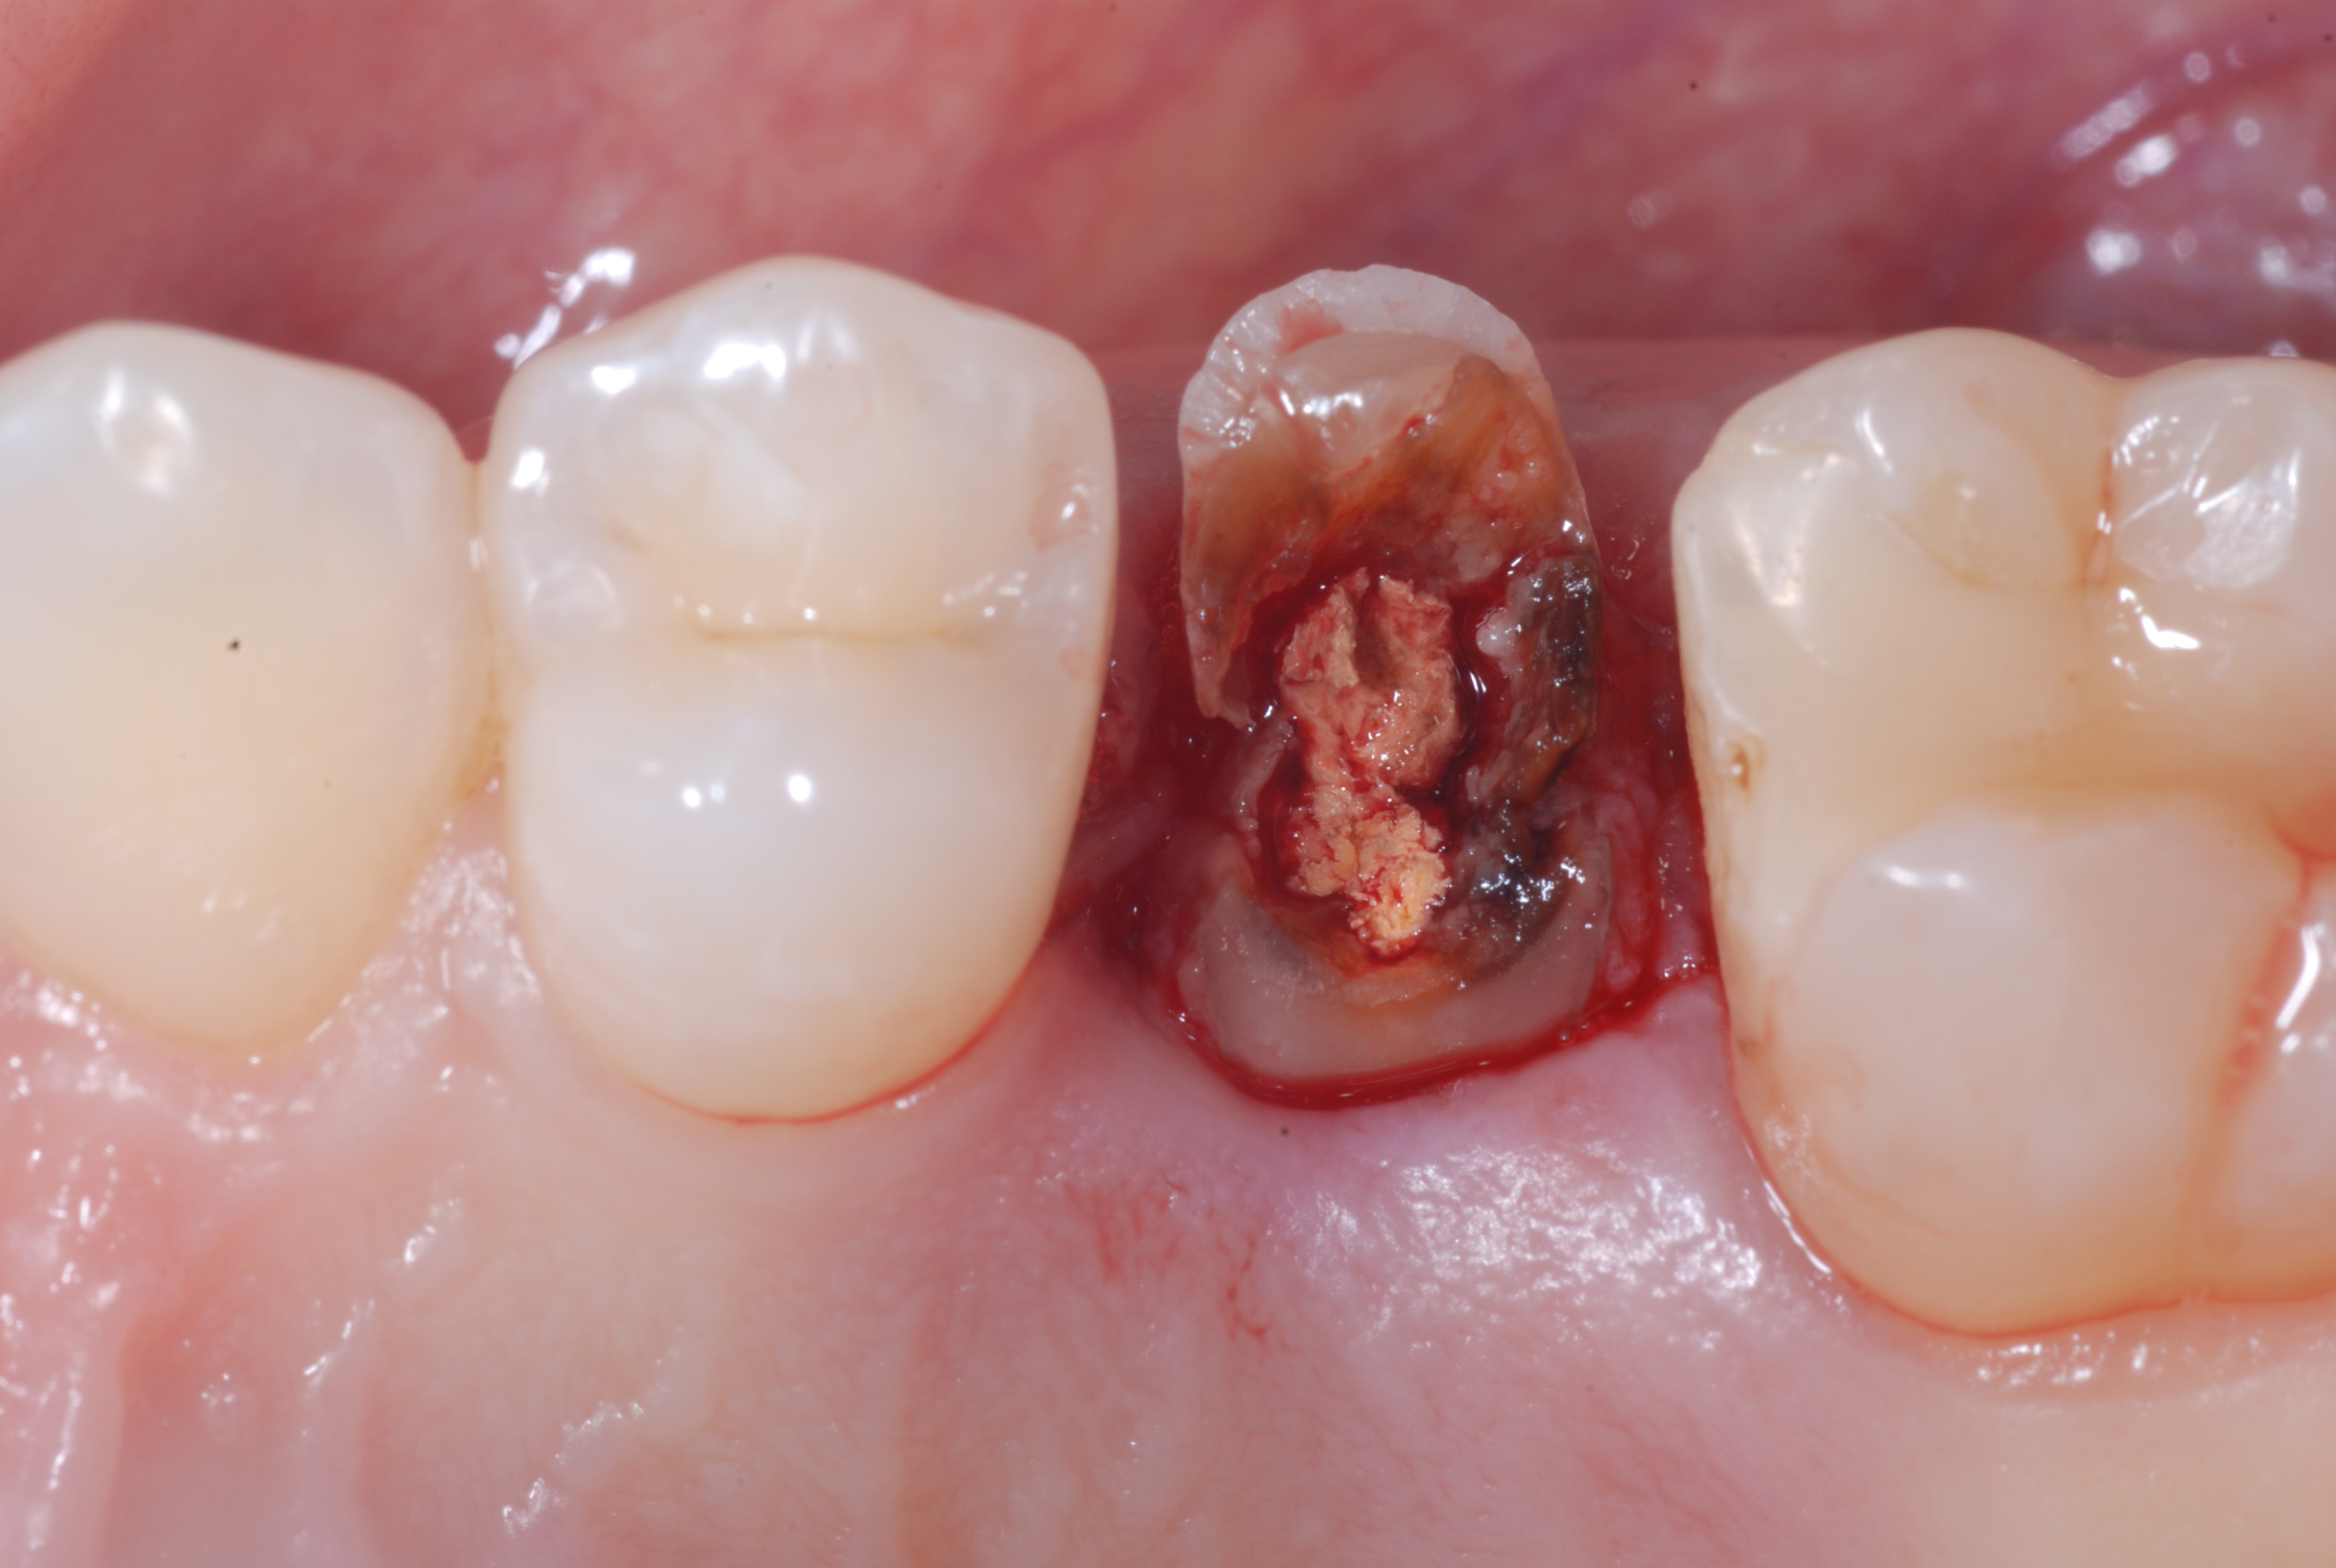

The patient was sent to me by a colleague knowing that I deal with surgical extrusion to avoid the extraction of the extremely compromised tooth 25. Once the possibilities, limitations, and risks of the technique and the possible options (such as orthodontic extrusion) had been explained to her and the colleague, they both agreed to surgically extrude the upper premolar.

The radiolucent area of the coronal portion of the root is evident, well below the bone crest from the radiographs. I also warned my colleague of the presence of numerous interproximal carious lesions.

Figure 1

Figure 2

Figure 1. Bite Wing X-ray and Apical X-ray of tooth 25 completely compromised by the carious process.Figure 2. Clinical image of tooth 25 totally destroyed at the coronal level.